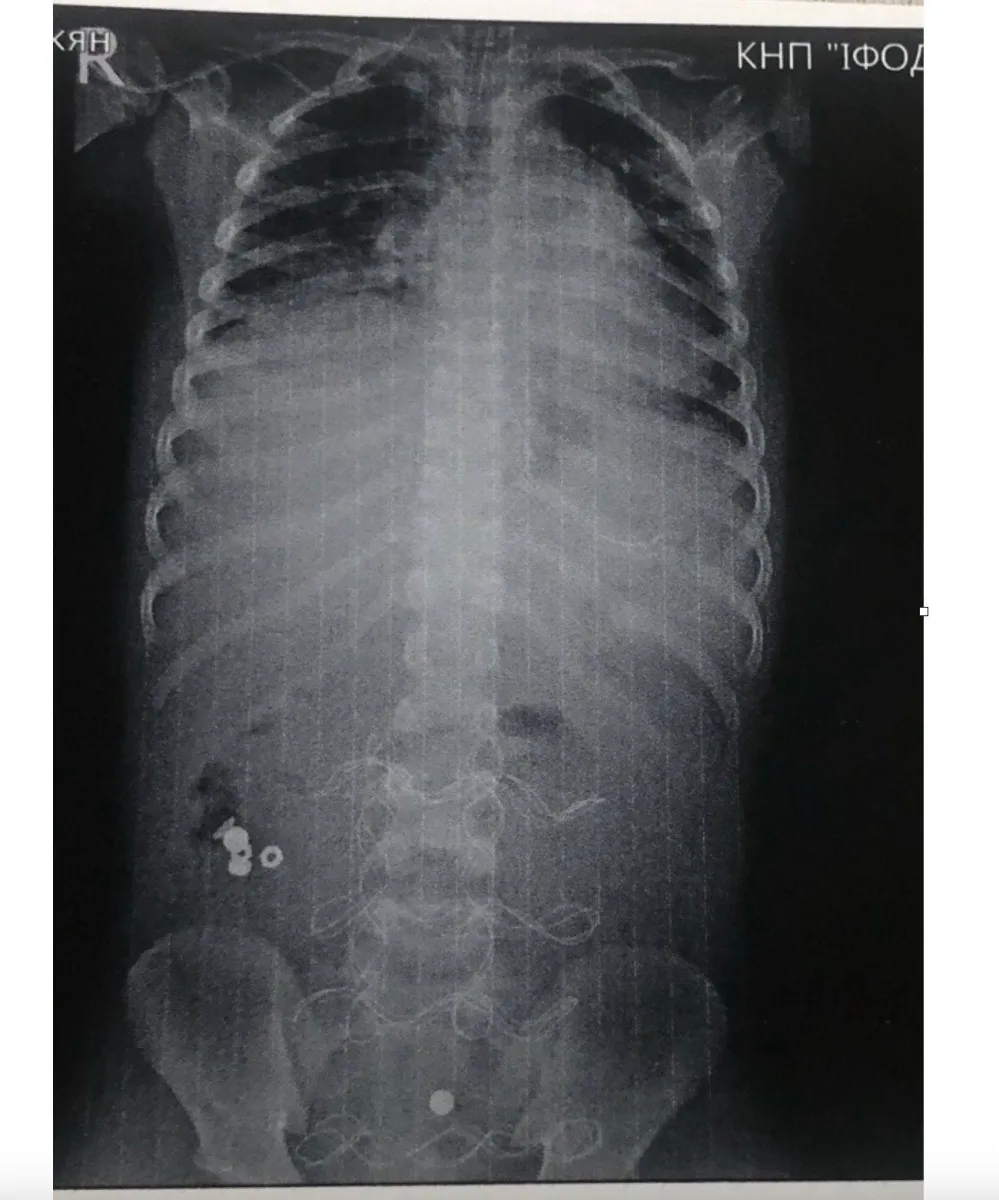

Дитину привезли до медичного закладу у вкрай тяжкому стані інфекційно-токсичного шоку з клінікою розлитого перитоніту. Як виявилось, хлопчик проковтнув батарейку, що спричинило перфорацію тонкого кишківника.

«Передопераційна підготовка тривала 12 годин. Всього було провели три оперативних втручання і лише на 20 добу дитину виписали з лікарні в задовільному стані», – повідомив директор Івано-Франківської обласної клінічної лікарні Тарас Мельник.